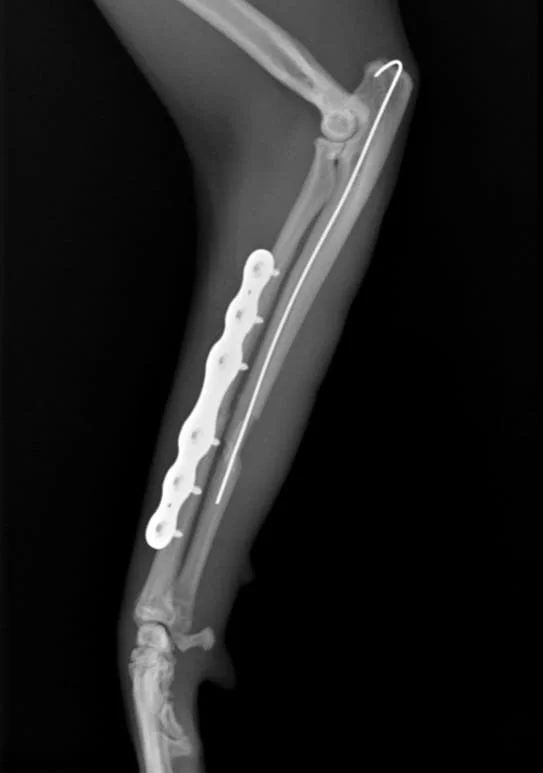

Surgical treatment with internal stabilization.

Cranio-lateral approach to radius & ulna.

Ulnar fracture reduction using 0.8mm k-wire,

radius fracture reduction with Fixin 1.9 mini-series V2102 locking plate with 6 screws.